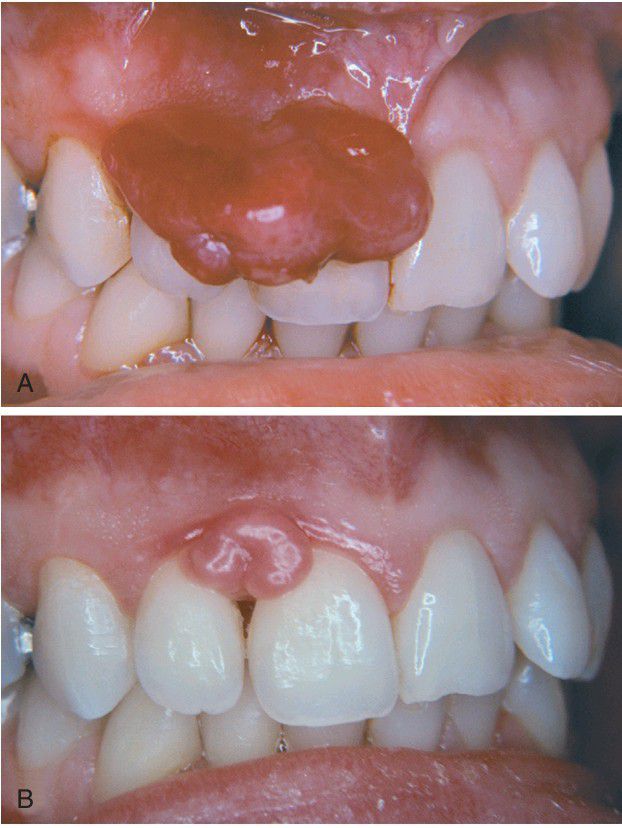

Pyogenic Granuloma

. A, Large gingival mass in a pregnant woman just before childbirth. B, The mass has decreased in size and undergone fibrous maturation 3 months after childbirth.